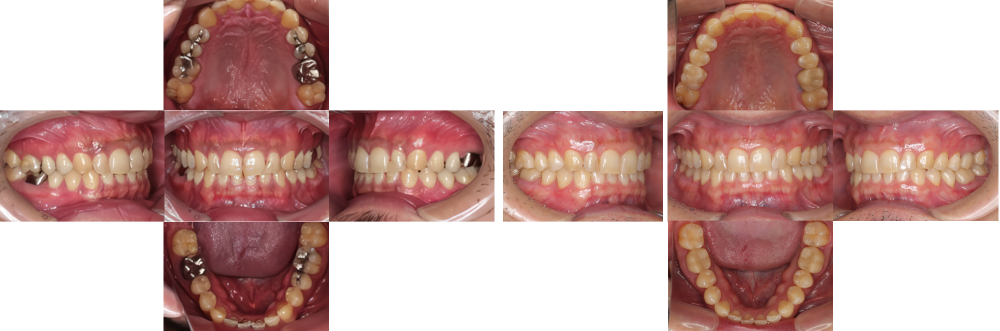

全顎保険治療

術前

術後

| 治療内容 | 全顎的に保険内で治療を行った |

|---|---|

| 治療期間・回数 | 約2.5年・約50回 |

| 治療期間・回数 | 約3年・約55回 |

| 費用 | 保険適用となります |

| 治療期間・回数 | 約1年4カ月・約34回 |

| 治療期間・回数 | 約1年4カ月・約21回 |